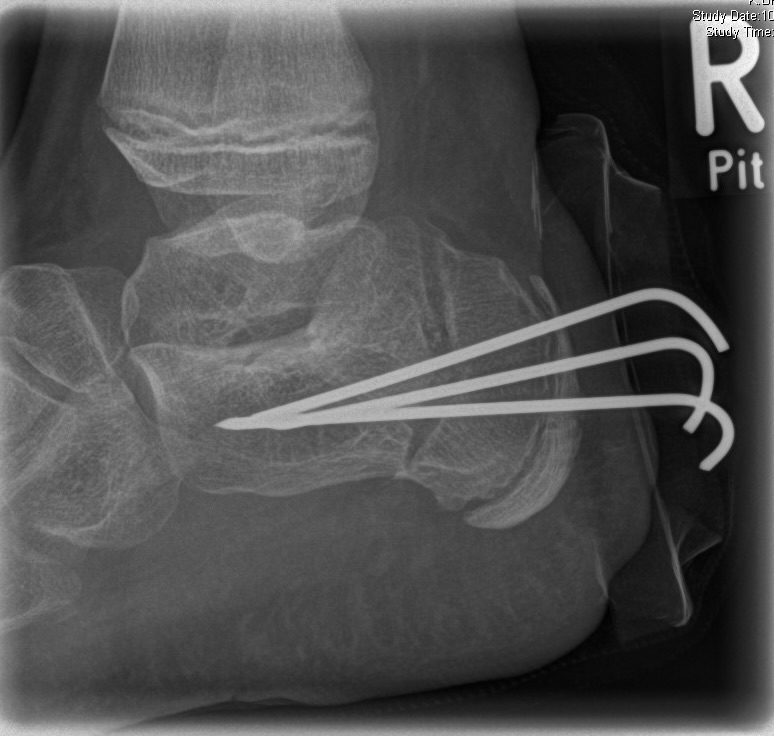

Zusätzlich schränken Wachstumsfugen die Wahl der Osteosynthese ein. Eine die Fuge kreuzende Osteosynthese ist ausschließlich mit Kirschner-Drähten möglich (Abb. 3).

Abb. 3 a-j: Beispiel einer Calcaneusverschiebeosteotomie mit offenen Wachstumsfugen und der entsprechenden Osteosynthese mit Kirschner Drähten. Lokalisation der Osteotomie (a), Lage der Fräse (b-d), Drahtlage mehrere Ansichten (e-h), Heilung der Osteotomie 4 Wochen postoperativ und Entfernung der Drähte (i-j).

Calcaneus-Osteotomie

Die minimalinvasive Calcaneusverschiebeosteotomie bietet eindeutige Vorteile gegenüber dem offenen Verfahren, sodass wir bei Kindern und Jugendlichen nahezu keine offene Verschiebeosteotomie mehr durchführen. Am Calcaneus liegt die offene Wachstumsfuge dorsal. Bei der Durchführung müssen Schenkel der V-förmigen Osteotomie daher etwas steiler angelegt werden, in einem stumpfen Winkel (siehe Abb. 3 a-j). Für die Osteotomie liegen unsere Patienten auf dem Rücken und der BV wird für die exakte Seitaufnahme eingestellt. Der Fuß lagert auf einem hohen OP-Kissen und die Osteotomie kann bequem mit einem langen Kirschner-Draht und einem sterilen Stift angezeichnet werden (Abb. 15).